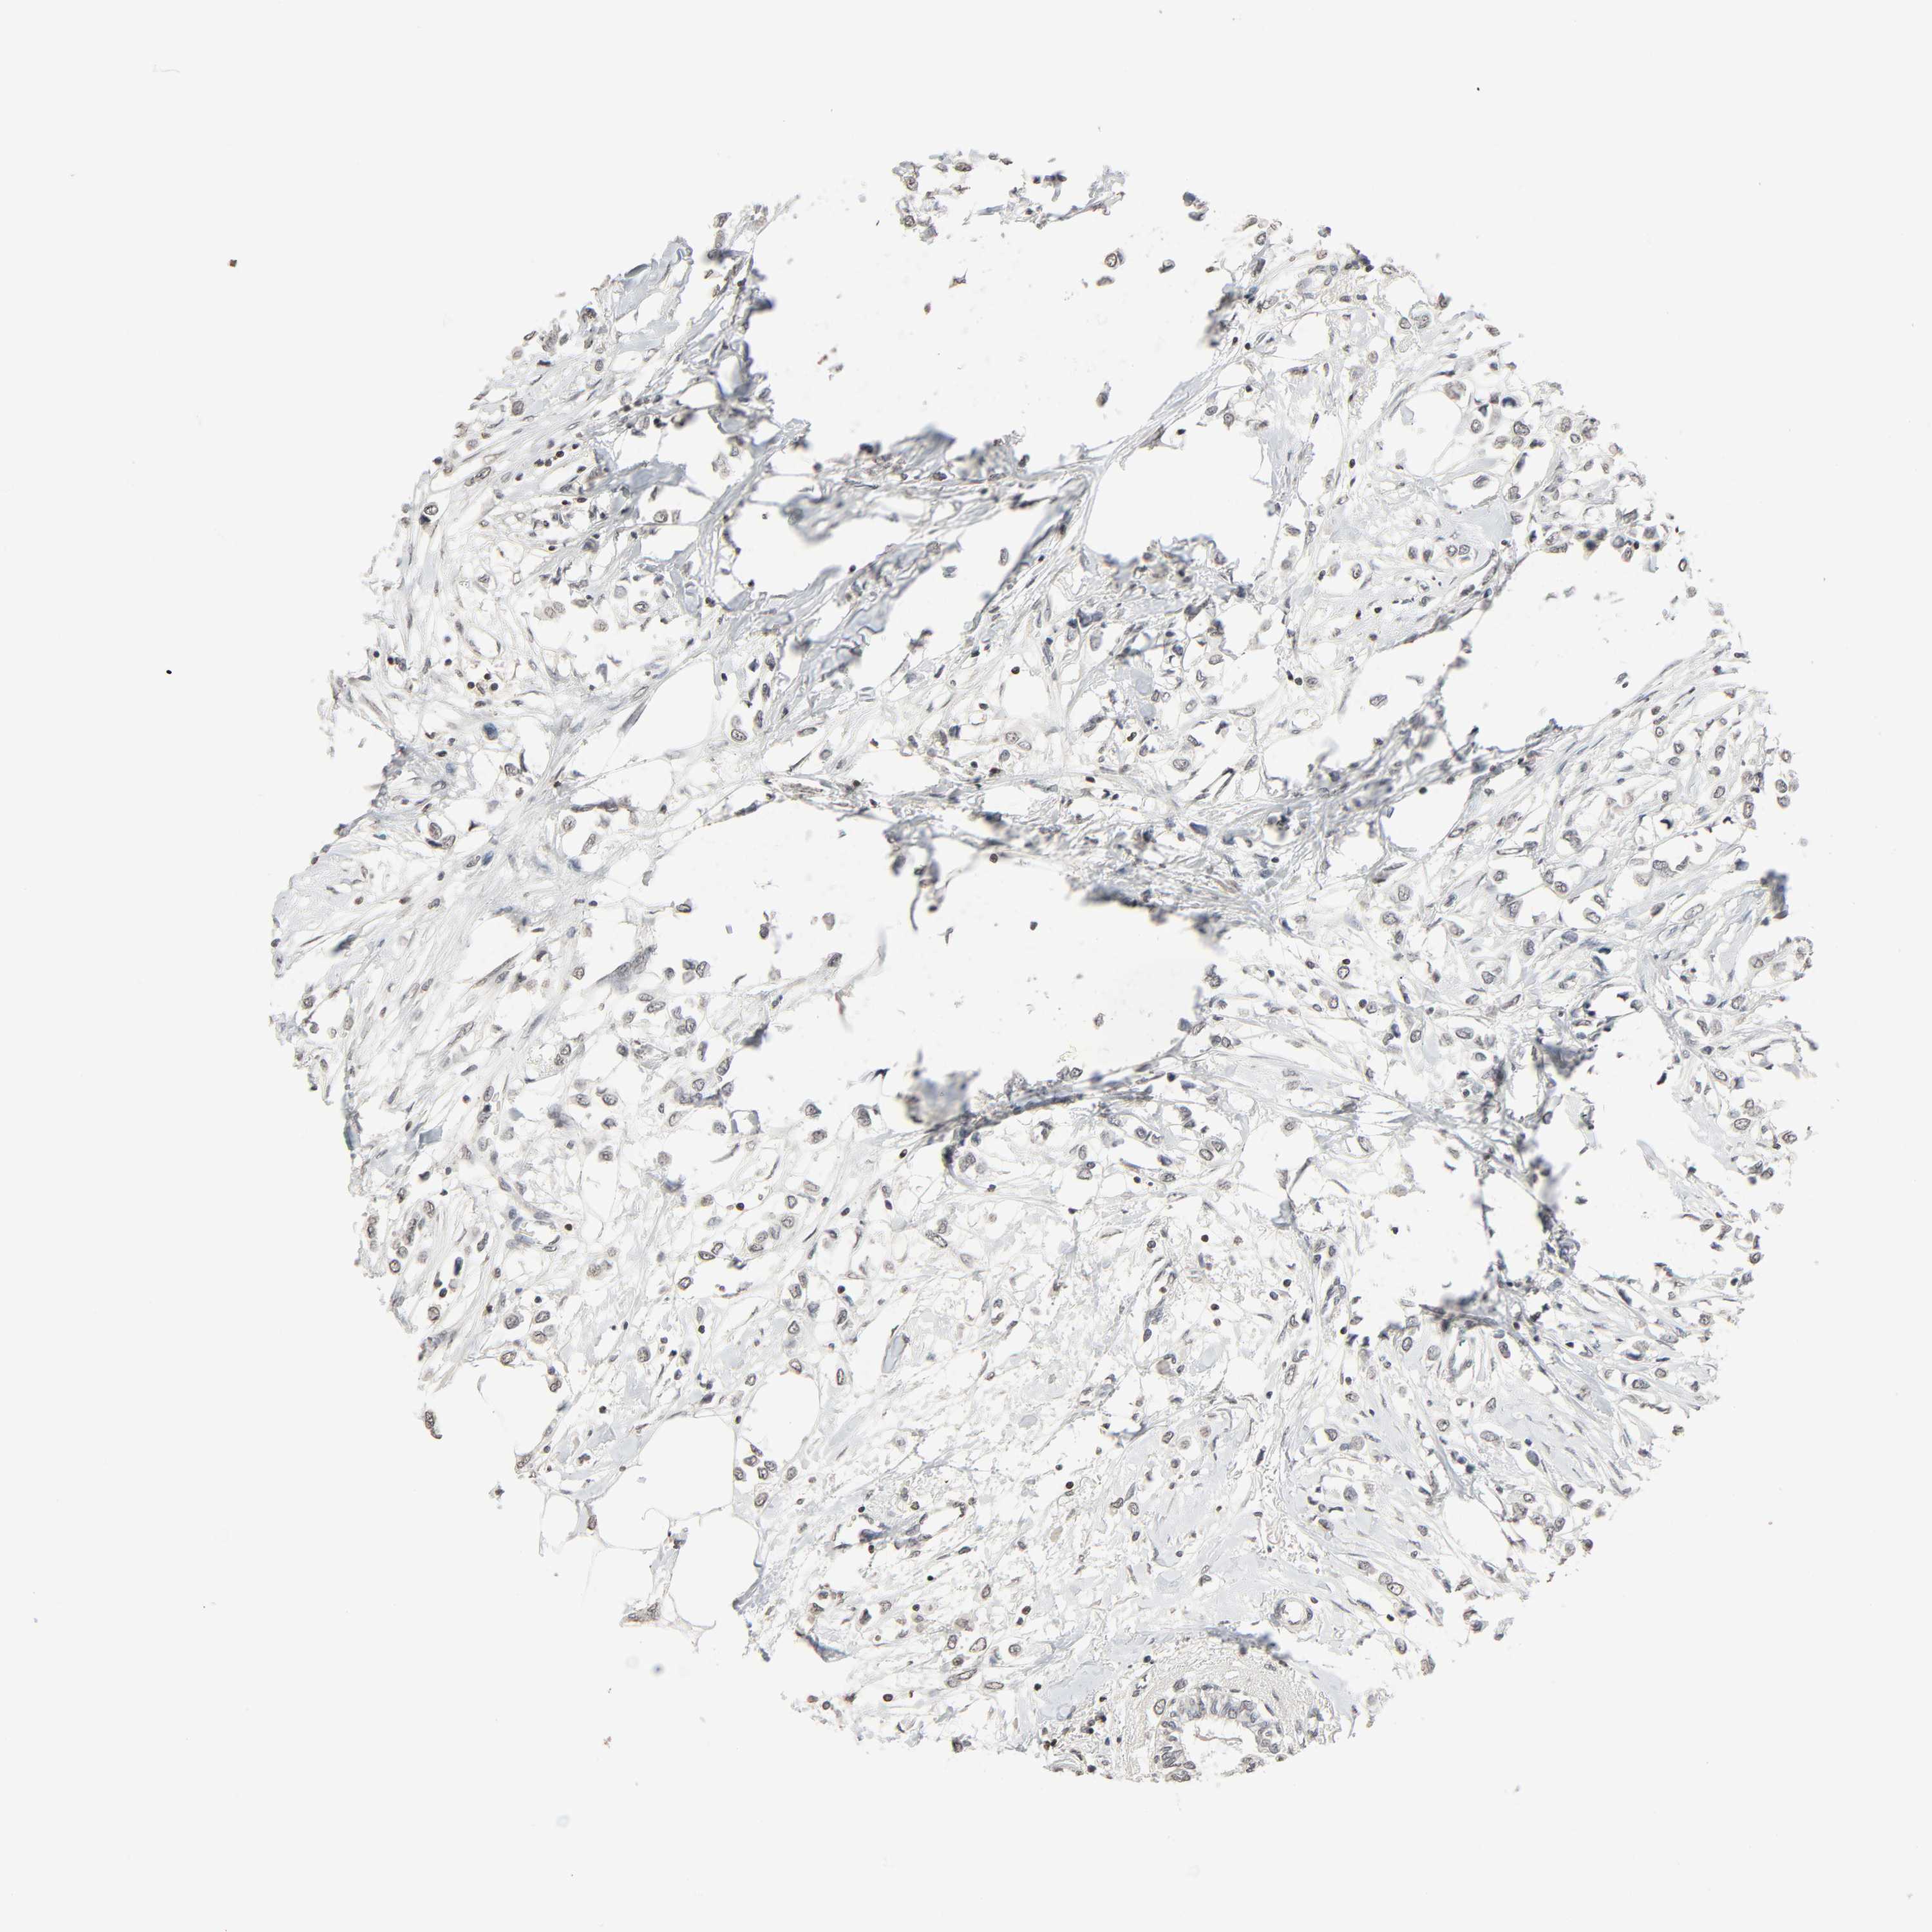

BRCA TCGA BRCA VALIDATION PROTEIN EXPRESSION